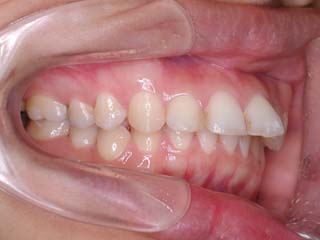

主訴:前歯が出ている

診断名:叢生を伴う上顎前突

かなり強い上顎前突を示します。その他の問題はなさそうですが、小臼歯抜歯だけでは上顎前突に対応しきれそうにありません。上顎大臼歯に最大限の固定が必要と考えられましたので、上顎左右の臼歯部に計2本の歯科矯正用アンカースクリューの植立を検討してみました。